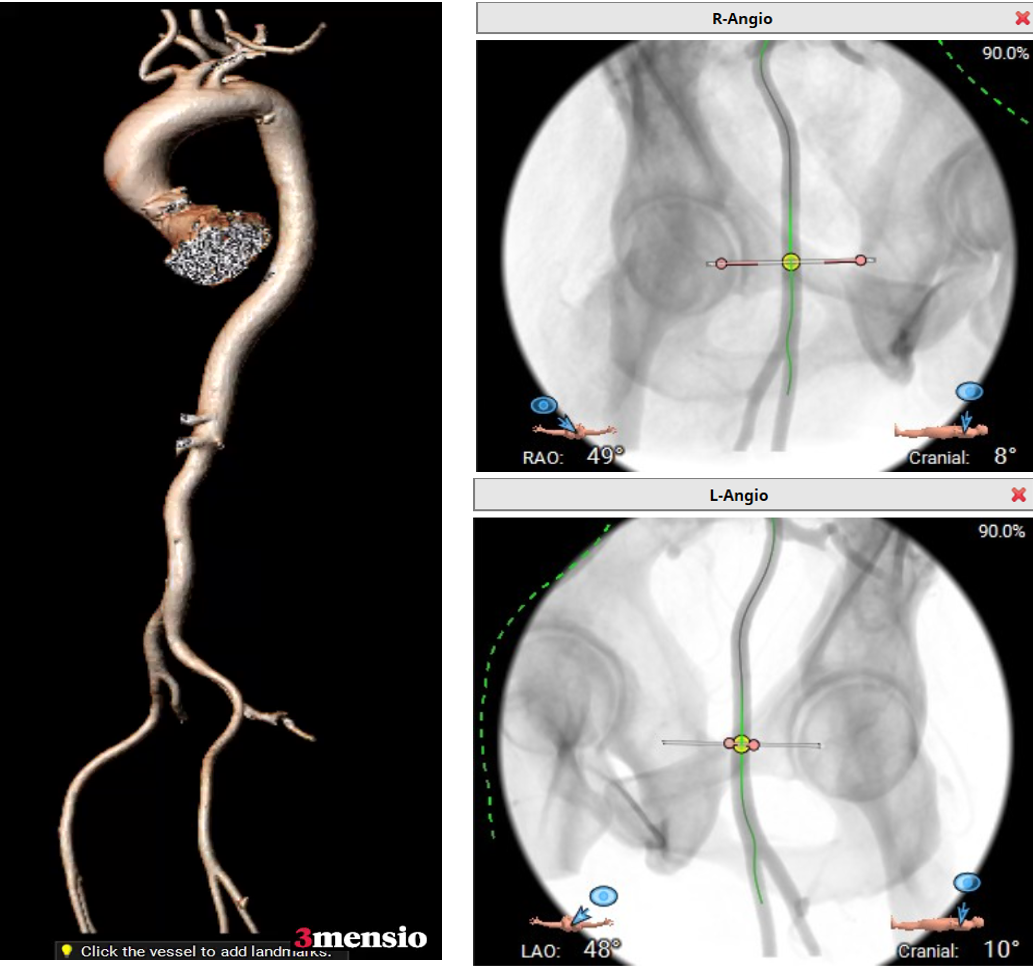

外周血管入路评估:右侧股动脉最小直径:5.9mm,左侧股动脉最小直径:5.7mm;无钙化。

面对Type 0型二叶式主动脉瓣狭窄这一高难度病例,王焱教授团队基于多模态影像学评估制定了精细的个体化策略。术前CT评估显示:患者瓣环面积376.7 mm²,主动脉窦部平均直径20.8 mm,窦管交界平均直径22.3 mm,瓣叶明显增厚伴中度钙化。团队综合评估后,为兼顾瓣膜稳定性和冠脉安全,创造性采用"Downsize策略",全麻下以右侧股动脉为主入路行TAV,选择20mm SAPIEN 3瓣膜,计划在90/10位置以标准容积或适当加量释放。